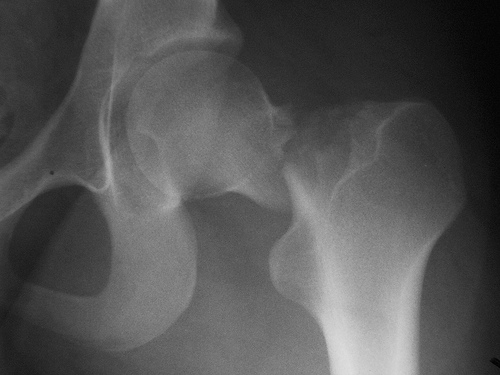

Fármacos y fracturas en los ancianos

23 agosto 2016

Un estudio halló que más del 75% de los pacientes fracturados recibían fármacos que aumentan el riesgo de fractura. Además, la mayoría los siguió utilizando después. JAMA Internal Medicine, 22 de agosto de 2016